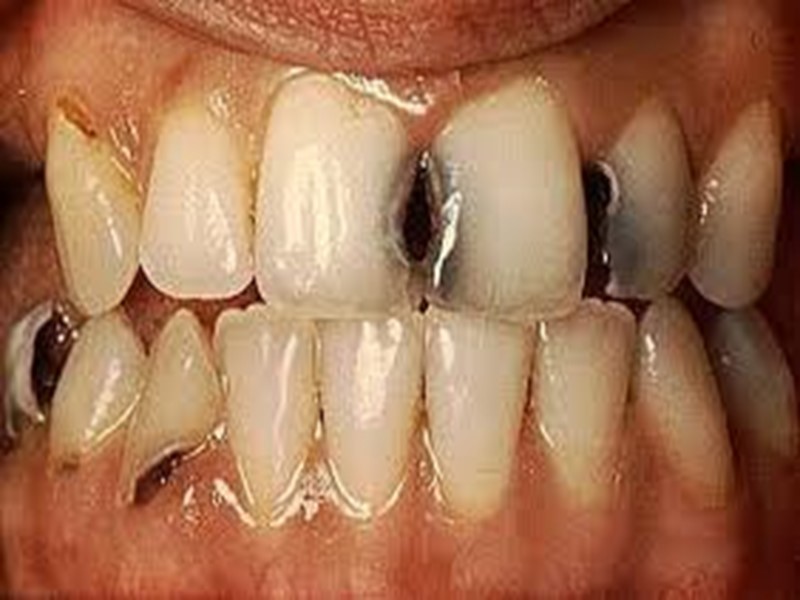

Классификация по локализации: Фиссурный кариес. Контактный (апроксимальный) кариес. Пришеечный (цервикальный) кариес. Циркулярный (кольцевой) кариес.

Пятый класс

Классификация кариозных полостей по Блеку 1 класс – полости, расположенные в области фиссур и естественных углублений (например, слепая ямка верхних латеральных резцов); 2 класс – полости, расположенные на контактных поверхностях моляров и премоляров; 3 класс – полости, расположенные на контактных поверхностях резцов и клыков при сохранении режущего края; 4 класс – полости, расположенные на контактных поверхностях резцов и клыков с нарушением углов и режущего края коронки; 5 класс – полости на губных, щёчных и язычных поверхностях, расположенных в придесневой части коронки. В последнее время выделяют 6 класс, который не описал Блек, это полости, расположенные на буграх моляров и премоляров и на режущем крае резцов и клыков